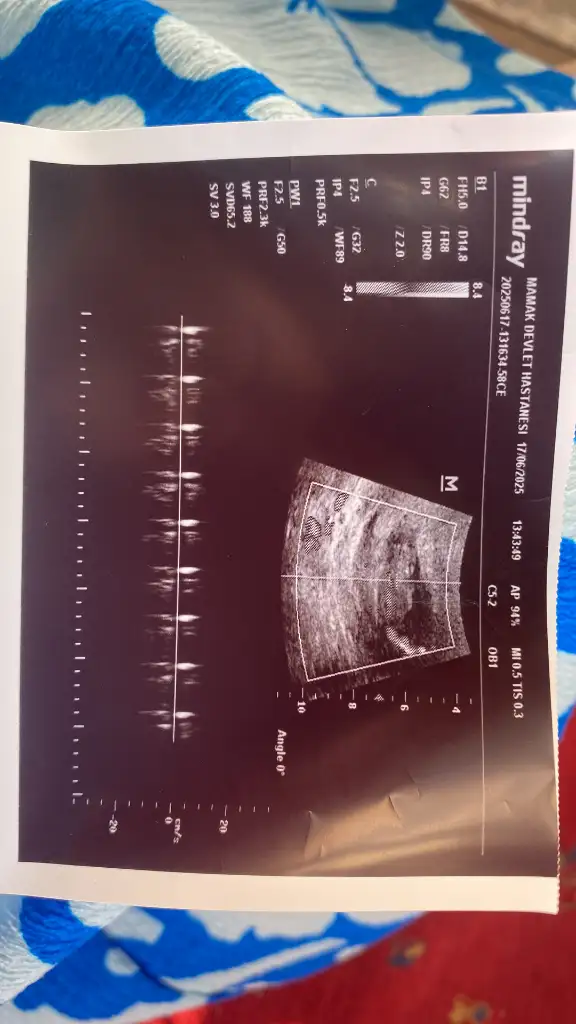

Rica etsem bana da tahminde bulunur musunuz 13+6

Eklentiler

• IMG20250620181644.webp

17,4 KB · Görüntüleme: 32